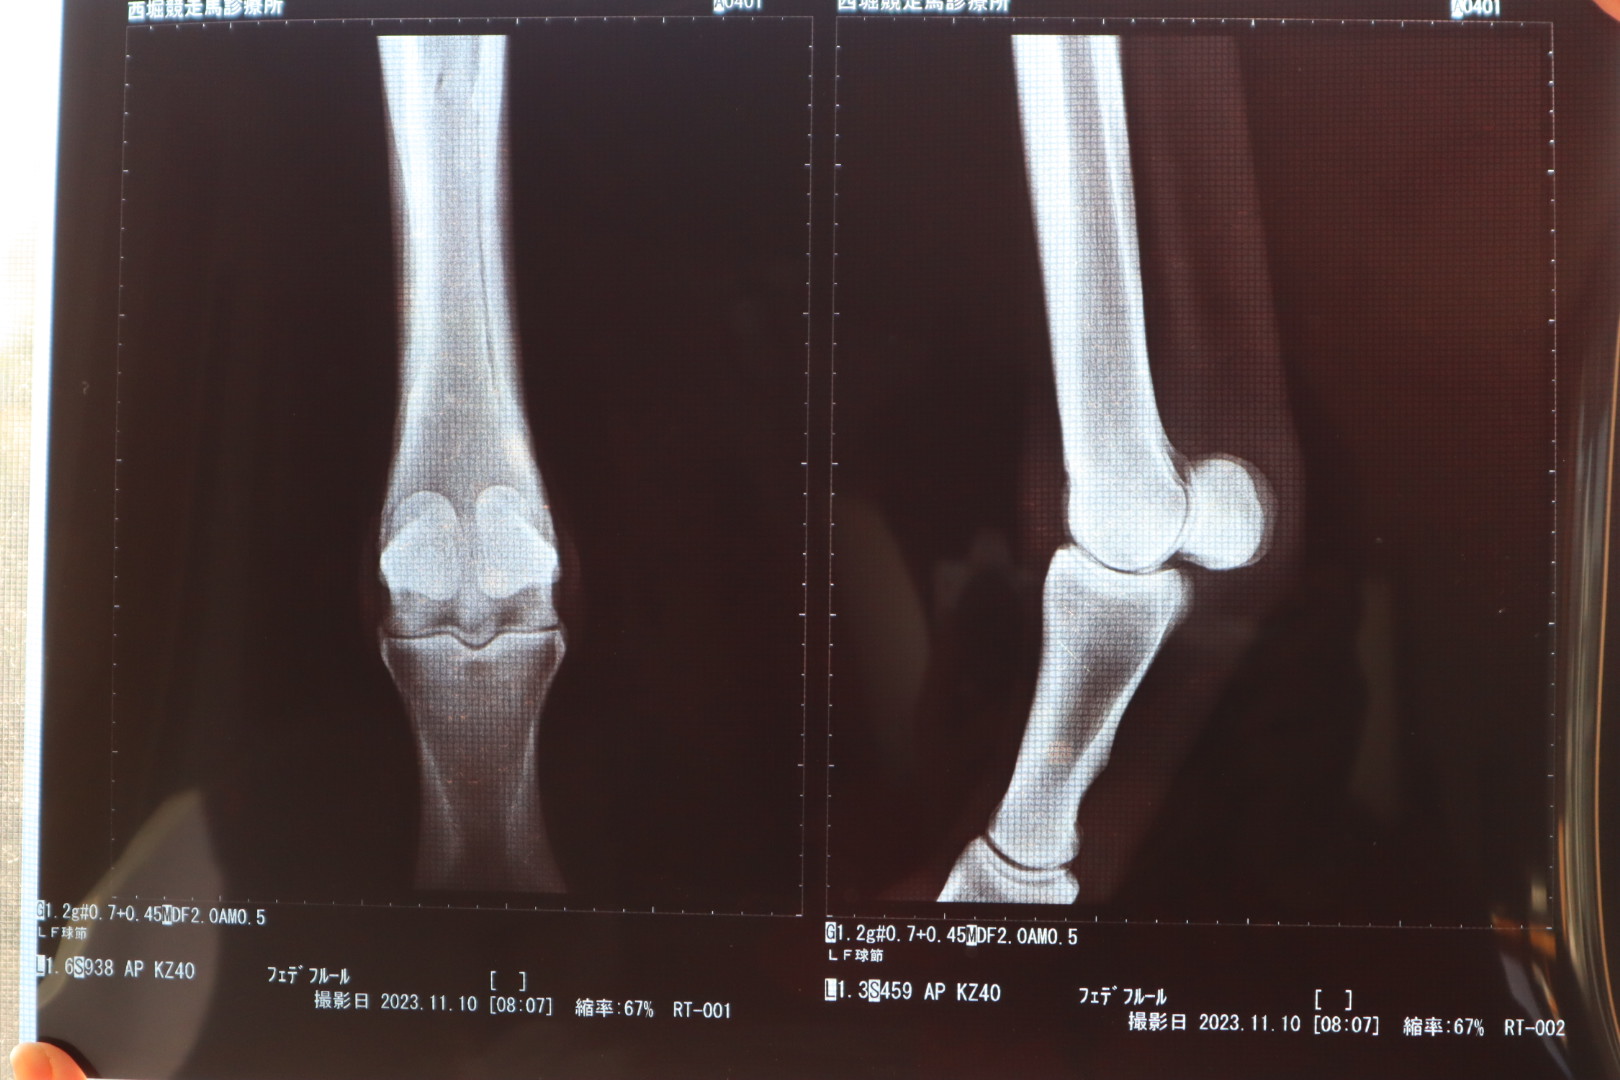

なお、オークション出品に伴い、2023年11月10日にレントゲン撮影を行ったところ、右前球節前面部に僅かに骨膜が確認されています。

※2022年3月8日(3歳時)調教後、軽度の跛行が見られたためレントゲン検査を行ったところ、右前第3中手骨にうっすらと骨折線が確認されました。事故見舞金12号(調教中の事故により事故発生の日から3ヵ月以上出走できなくなった場合)の適用を受けています。